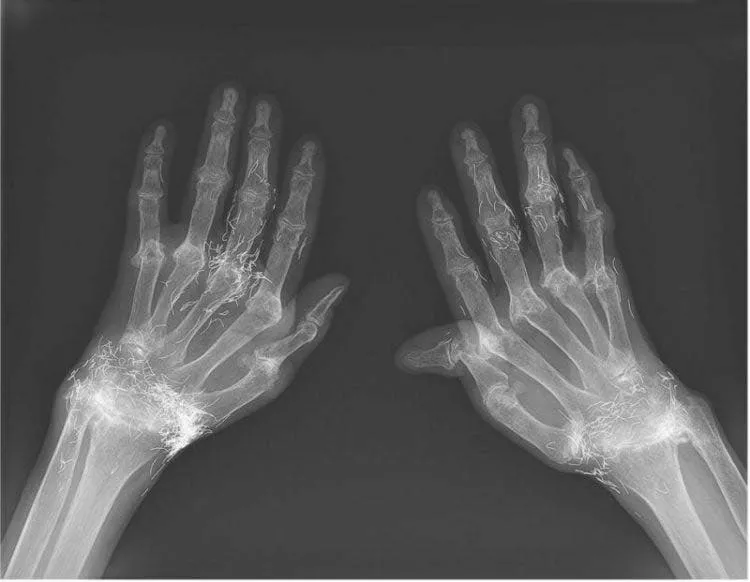

وأظهرت صور الأشعة السينية وجود سماكة وتصلب في الجزء الداخلي من قصبة الساق ونمو عظمي في الركبة، وهي علامات شائعة لهشاشة العظام. إلا أن المفاجأة كانت في اكتشاف مئات من الخيوط الذهبية الدقيقة المزروعة داخل الأنسجة المحيطة بالمفصل.